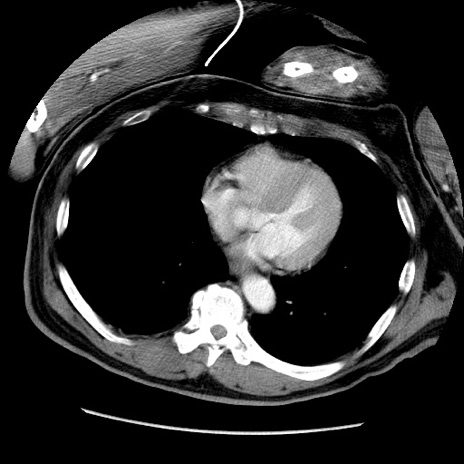

症例22(横断像)

【症例】50歳代男性

【主訴】腹痛

【現病歴】AVMからの被殻出血のため回復期リハ病棟入院中。 本日午後3時頃急に下腹部痛が出現した。

【既往歴】AVM、被殻出血、虫垂炎、高血圧

【身体所見】意識晴明、左半身不全麻痺、会話の理解は良好、36.5°C、腹部:膨隆、全体に板状硬、下腹部正中に圧痛点あり、反跳痛-、筋性防御不明、右下腹部にope scar

【データ】WBC 9400、CRP 0.06